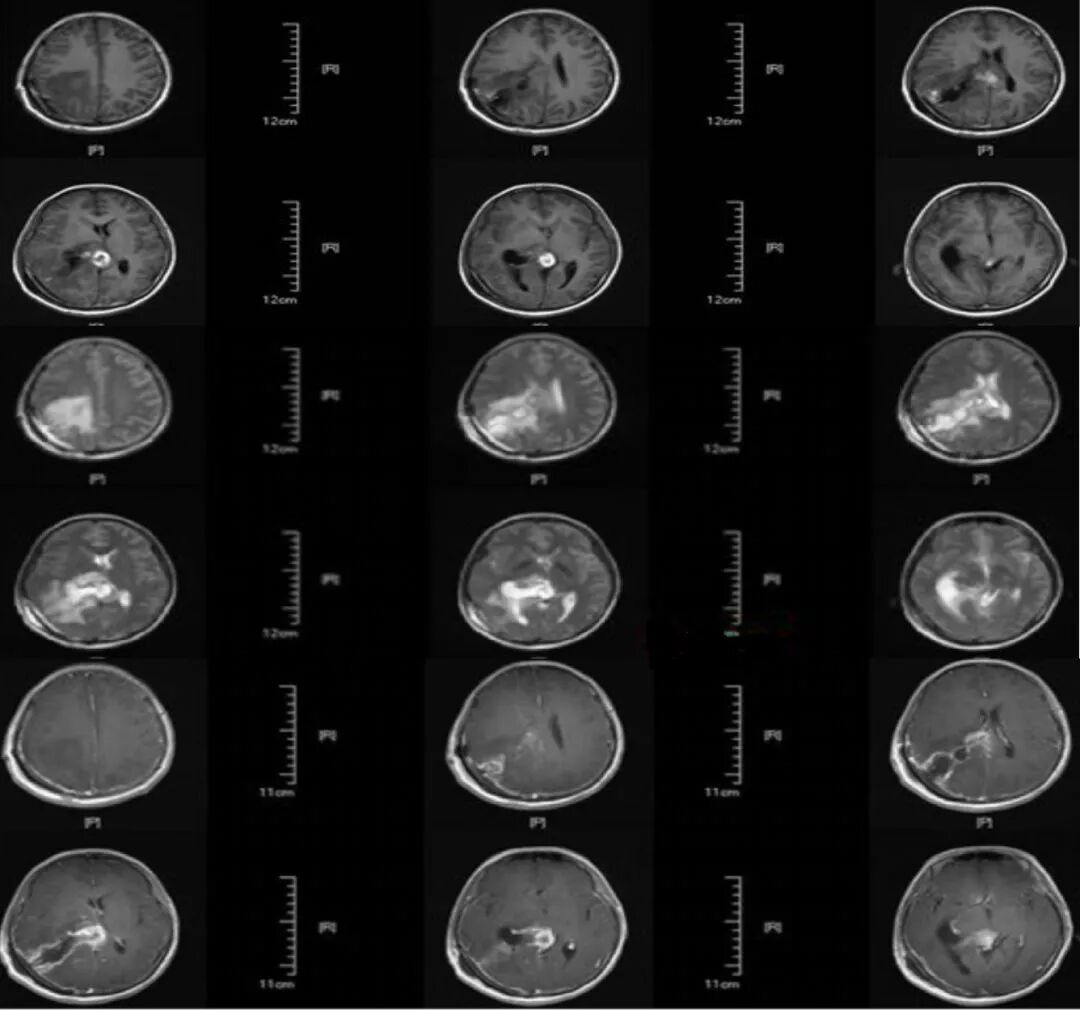

既往病史:2月余前因右侧侧脑室肿瘤,见(图1)行右侧顶枕三角区入路肿瘤切除术,术中见肿瘤呈灰白色、质地韧、血供一般,显微镜下全切除肿瘤,术后病检结果为脑膜瘤、WHOI级。

图1. 磁共振显示右侧侧脑室肿瘤,肿瘤大小约5.0 cm×6.5 cm,呈强化明显。